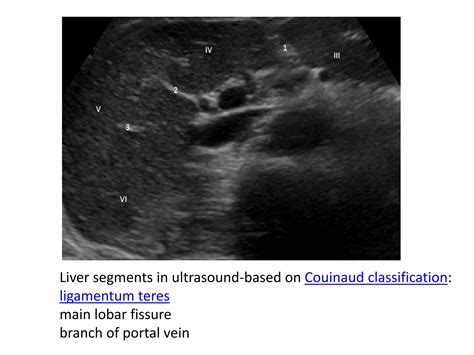

In the field of diagnostic radiology, the Ligamentum Teres Liver acts as a vital anatomical marker. When interpreting CT scans or MRIs, radiologists use the ligament to orient themselves within the hepatic segments. It effectively divides the left lobe of the liver into medial and lateral segments, which is crucial for identifying localized pathologies such as tumors or focal fatty infiltration.